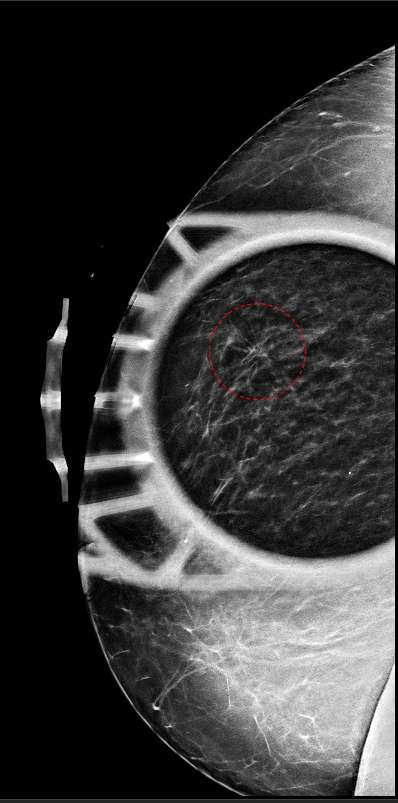

Additional spot compression views of the architectural distortion seen on craniocaudal mammogram view shows persistence of the architectural distortion within the lateral right breast (red circle). This appearance is consistent with a real distortion of the breast parenchyma and not simply overlapping normal fibroglandular tissue.

Figure 2: Additional spot compression views of the architectural distortion seen on craniocaudal mammogram view shows persistence of the architectural distortion within the lateral right breast (red circle). This appearance is consistent with a real disto

Figure 2 shows spot compression tomosynthesis of the architectural distortion shown in Figure 1. Note how the region of architectural distortion does not appear to “smooth out”, but rather retains a fairly stable appearance compared to Figure 1.